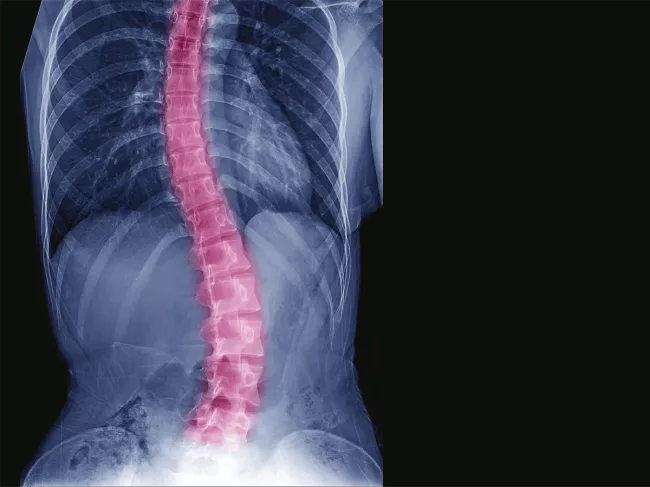

scoliosis-spine-orthopedic.png